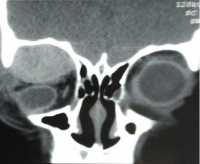

Most frequent involvement IR>MR>SR>LR. Superior Ophthalmic Vein may be enlarged due to apical compression | Axial and coronal section of non-contrast CT images of orbit showing three different patterns of TED. a) Bilateral fusiform enlargement of the extraocular muscles sparing the tendinous insertion with posterior crowding (orange stars) b) Bilateral fusiform enlargement of the extraocular muscles sparing the tendinous insertion along with increased orbital fat. c) Bilateral increased orbital fat (denoted by increase of hypodense areas of fat attenuation). EOM appears normal. |